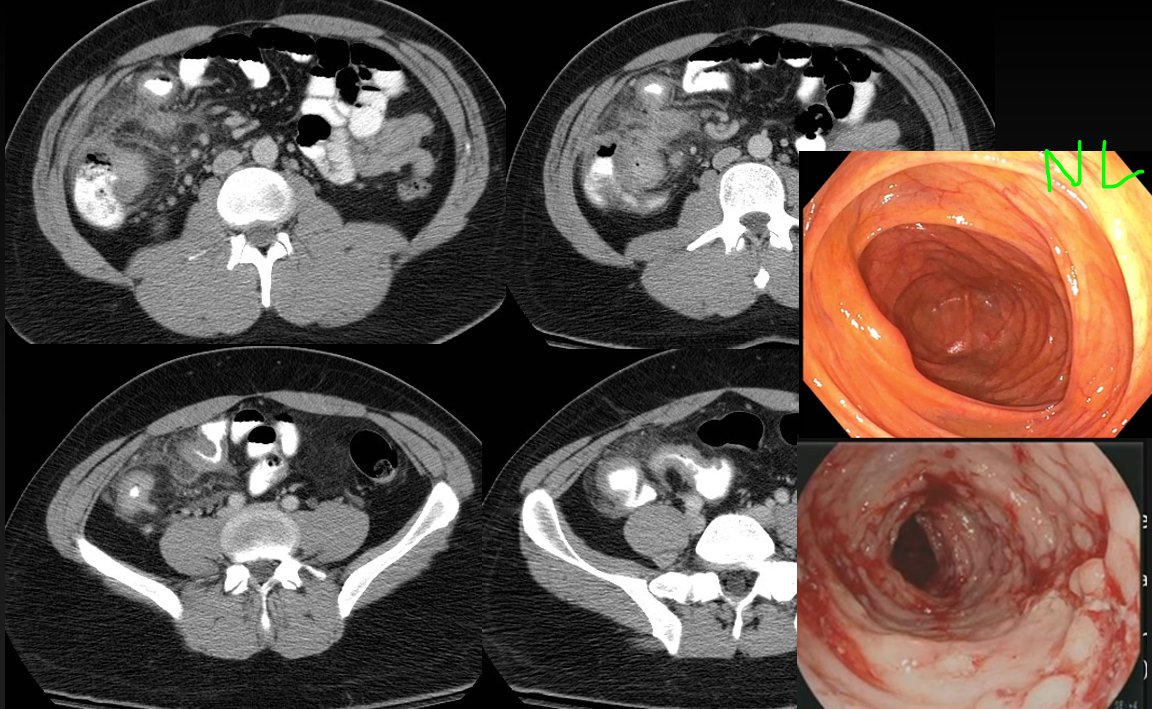

✨Up Next in our Member Spotlight Series - featuring Dr. Rocky Saenz! His passion for education has inspired numerous medical students and radiology residents. Dr. Saenz has made significant strides for DOs and radiologists, enhancing their recognition in the medical field.